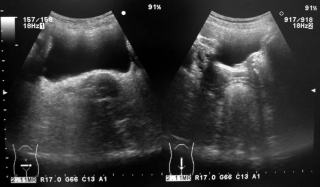

尿路結石の関与を疑い腹部エコーを行いました。腎臓には異常所見は認めませんでした。

腹部エコー

膀胱内にも結石は認めませんでした。